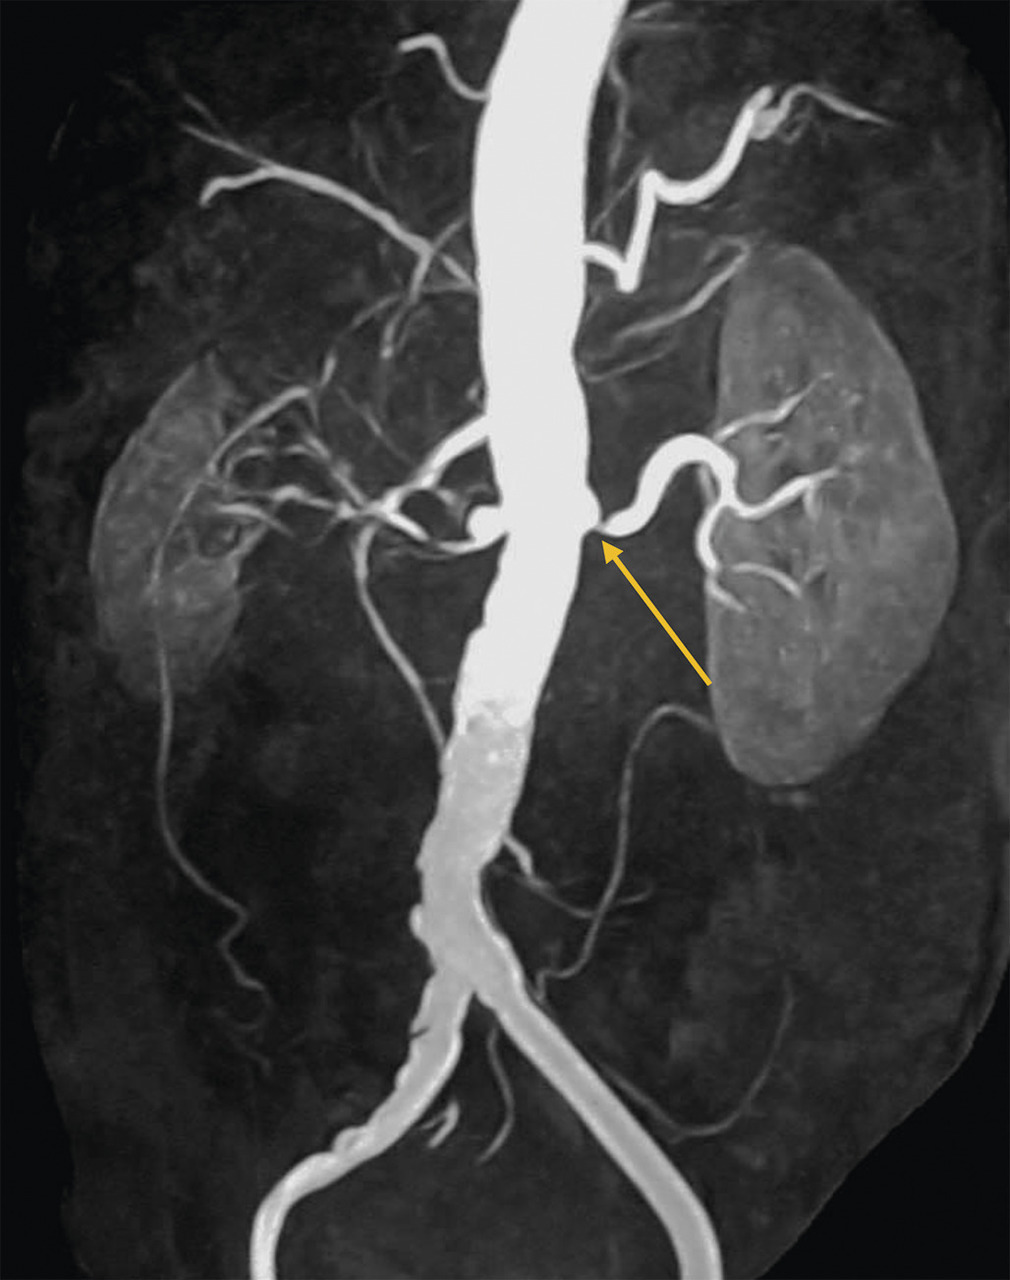

L’échographie-Doppler, l’angio-tomodensitométrie (angio-TDM [fig. 2] et l’angio-imagerie par résonance magnétique (angio-IRM) [fig. 3] permettent le diagnostic de sténose de l'artère rénale. Ils estiment à la fois le degré de sténose (exprimé en pourcentage de réduction du diamètre) et l’impact sur la vascularisation d’aval. Ces 3 examens sont validés et recommandés en première intention. Leur utilisation dépend de l’accessibilité et des habitudes locales. Il est à noter que l’écho-Doppler, très sensible et spécifique dans la sténose de l'artère rénale athéromateuse sous réserve d’un opérateur entraîné, est de sensibilité imparfaite dans la fibrodysplasie, dans laquelle l’angio-TDM est l’examen de référence.

Dans la sténose de l'artère rénale athéromateuse, on retrouve une plaque habituellement unique, plus une moins calcifiée, ostiale, proximale ou tronculaire, responsable d’une réduction du diamètre endoluminal d’une ou des artères rénales (fig. 2 et 3).

En cas de fibrodysplasie, les lésions sont multiples, distales, souvent bilatérales, avec aspect en « collier de perles » (fig. 4). Il est recommandé, dans cette pathologie qui est souvent multifocale, de rechercher d’autres lésions artérielles (sténoses ou anévrismes) au niveau des artères digestives, cervicales et intracrâniennes.